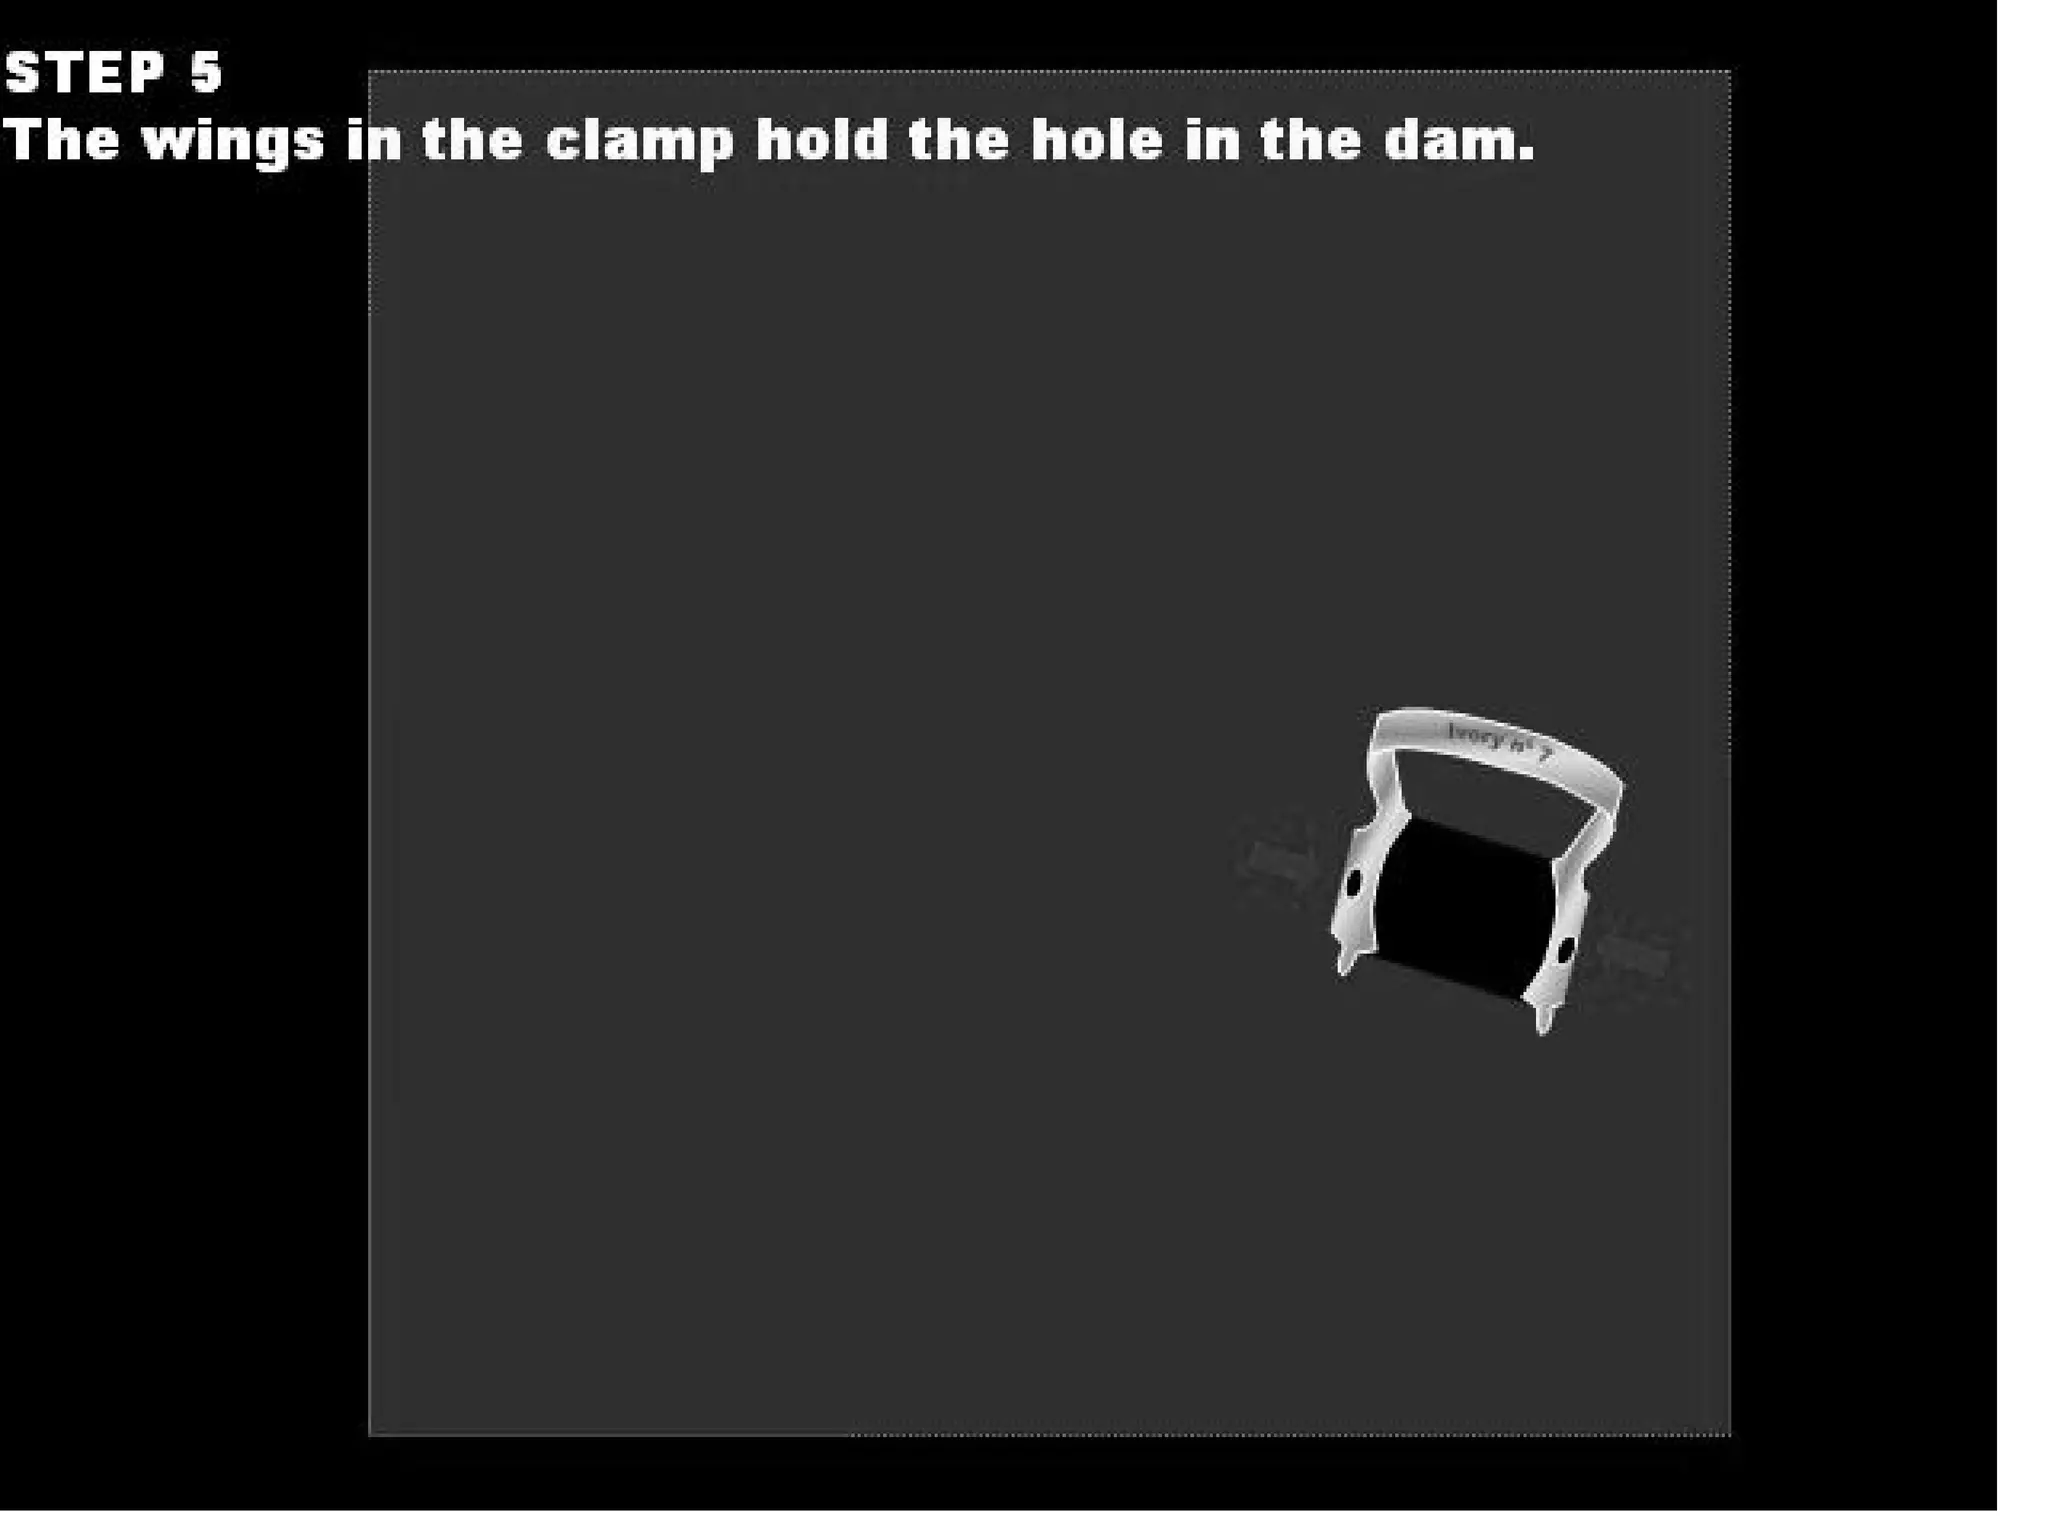

This document discusses the materials and components used for rubber dam isolation in dentistry. It describes the different types of rubber dam materials including color options and napkins to absorb moisture. It also outlines the tools needed such as punches to make holes, templates and stamps to guide hole placement, clamps to secure the dam, and other accessories like wedges and lubricant. Finally, it provides guidance on punching holes for different types of teeth and properly placing clamps in the rubber dam.